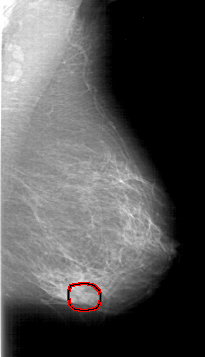

FILE: D_4189_1.LEFT_CC.OVERLAY

TOTAL_ABNORMALITIES 1

ABNORMALITY 1

LESION_TYPE CALCIFICATION TYPE AMORPHOUS DISTRIBUTION CLUSTERED

ASSESSMENT 0

SUBTLETY 2

PATHOLOGY MALIGNANT

TOTAL_OUTLINES 1

BOUNDARY